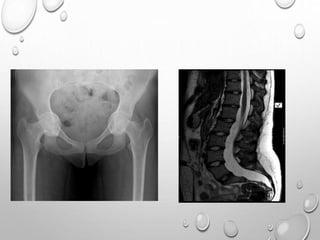

PELVIS

SMALL

ILIA ARE SHORT CAUDALLY

HORIZONTALLY PLACED ACETABULLA , THICKENED Y CARTILAGE

• 1. DYSPLASTIC OR SQUARE

ILIAC BONES

2. NARROW SACRO-SCIATIC

NOTCHES

3. FLAT BILATERAL

ACETABULAR ROOFS

4. SHORT BOTH FEMORAL

NECKS

5. CHAMPAGNE GLASS-

SHAPED PELVIC CAVITY

CONSIDERING THE INCIDENCE AND POTENTIAL SEVERITY OF NEUROLOGIC

SYMPTOMS ASSOCIATED WITH FORAMEN MAGNUM STENOSIS, A BASELINE MRI

IS STRONGLY RECOMMENDED IN INFANCY.

MRI SHOWING CERVICOMEDULLARY COMPRESSION AT FORAMEN MAGNUM